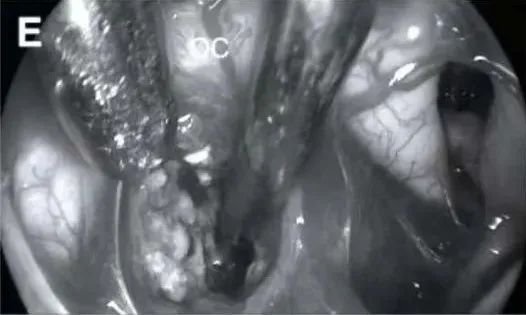

(E)切换至30°内镜观察:切换使用30°内镜,观察视交叉 (OC) 后方的肿瘤情况。此步骤旨在更清晰地观察肿瘤与周围结构的关系,特别是视交叉后的部分。